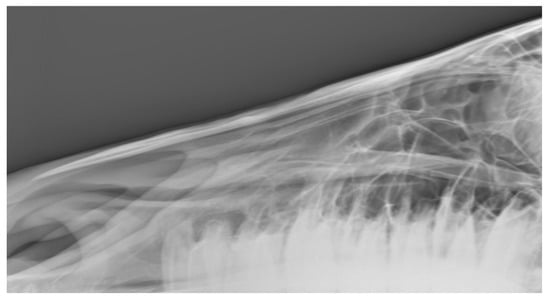

Figure 5. Radiographs showing the nasal bones of a horse in which radiologists (n = 2) agreed there was bone thinning that was: (a) typical of affected horses and (b) moderate.